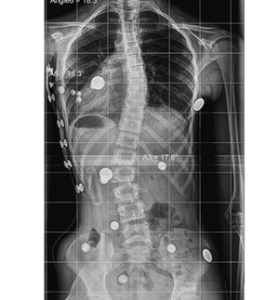

pe-300-rx-after